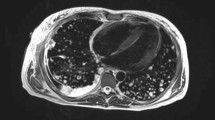

The role of computed tomography (CT) in the diagnosis of IA, or indeed any mould that causes infection localised to the lungs, is well established. The ESCMID-ECMM-ERS guideline advises ‘thin-section’ chest CT as the imaging modality of choice for patients at risk of IA and with clinical signs suggestive of the same [12••]. Where this is not feasible, pulmonary MRI has been suggested as an alternative [21, 22]. Given the atypical presentation pattern of invasive mould infection in immunodeficient children, it would be prudent to also include the paranasal sinuses in any scheduled chest imaging study [23•].

On chest CT, the classical features of halo sign (in the early phases of infection), reverse halo sign, nodules of > 1 cm diameter, alveolar consolidation, air-crescent sign, and centrilobular nodules with tree-in-bud appearance should be observed in IA and may be observed with other invasive moulds [24,25,26]. Unfortunately, in children, many of these features are not observed and it has long been proposed that any new CT changes should prompt the clinician to consider IFD and initiate antifungal treatment [11].

For select patient groups in whom IFD is considered probable rather than possible, for example those with a severe inherited primary immunodeficiency (CGD or severe combined immunodeficiency SCID), clinical features of IFD and/or who meet specific mycological criteria such as positive biomarkers, it might also be reasonable to consider CT or MRI brain [10•]. This is particularly important in the setting of mould-active prophylaxis which can encourage the emergence of indolent and atypical fungal pathogens [27,28,29]. Mould-active prophylaxis has become increasingly commonplace in the management of children with primary immunodeficiency, specifically CGD. Haidar et al. describe a young man with X-linked CGD, taking prophylactic posaconazole, who presented with disseminated Phellinus tropicalis of the lungs and brain [29]. De Ravin et al. outline a similar case involving a 10-year-old boy with CGD, prescribed prophylactic itraconazole, who subsequently developed a paraspinal fungal mass attributed to Phellinus spp. [30•]. Thus, whilst central nervous system (CNS) imaging is not mandated in any published guideline, unless localising signs are present, it is important to remember that CNS manifestations of fungal disease occur more frequently in vulnerable patients. Early diagnosis improves outcome and clinicians should remain vigilant in their diagnostic efforts to exclude fungal CNS disease.